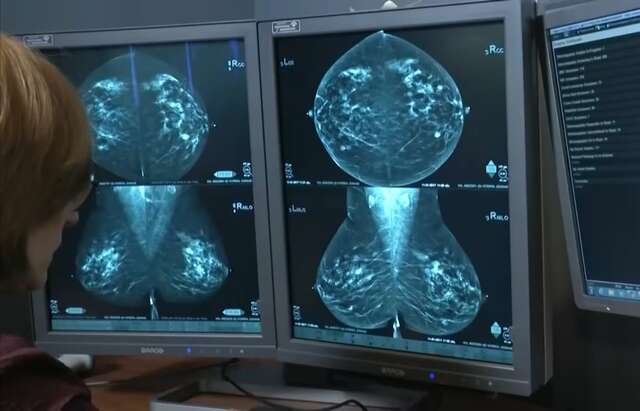

Ela alerta sobre a importância do diagnóstico precoce, por ser uma das principais ferramentas para aumentar as chances de cura do câncer de mama: “As mulheres não estão fazendo a mamografia. É a mamografia que permite a gente fazer diagnóstico precoce [...] Hoje a gente fala de 95% de chance de cura quando a gente acha pequenininho”, afirma.